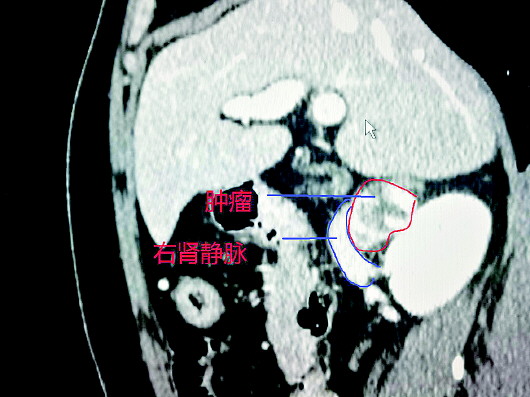

另外,肿瘤被腹膜后各大血管团包绕,CT显示其位于下腔静脉后方并将这支腹腔最粗的静脉压瘪,其下方紧邻右肾静脉,后上方毗邻右肾动脉。肿瘤游离要绝对避免上述血管的损伤,可谓“刀尖上的舞蹈”,一旦手术开始就没有后路,只许成功不许失败,不容丝毫意外发生。

经过12天的充分术前准备,5月12日,患者在全麻下进行经腹腔镜下腹膜后肿瘤探查、切除术。熊晖与潘美洲主刀,经过几个小时的奋战,顺利取出标本,成功完成手术。术中患者生命体征平稳,无明显波动,出血约100ml。台下切开标本,实性,包膜完整,约5×4×2cm大小,呈分叶状。病理经山东省立医院病理科免疫组化会诊,确诊为右侧肾上腺嗜铬细胞瘤。